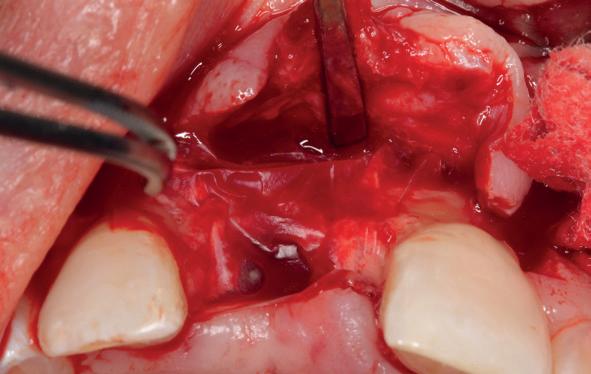

Na het klinische onderzoek volgde het röntgenologisch traject. De CBCT liet precies zien wat we al vreesden: een front waarin het bot onregelmatig was, duidelijke radiolucenties rond de pijlers en een infectiegebied dat zich onder vrijwel de gehele brug had verspreid. Tegelijkertijd was er ook potentie. Net voldoende botstructuur om immediate implantaatplaatsing te overwegen, mits alles perfect gepland zou worden.

Die planning gebeurde in R2Gate, niet als technologische “fetish”, maar als noodzakelijk hulpmiddel. Met behulp van intra-orale scans, foto’s en CBCT-data bouwden we stap voor stap het verhaal van haar mond op. Wat was er misgegaan, wat was er nog mogelijk en hoe konden we haar bestaande brug kopiëren en verbeteren tot een tijdelijke oplossing die dezelfde dag functioneel zou zijn.

Terwijl ik door de digitale lagen bladerde, werkte mijn assistent rustig naast me. Geen grootse momenten, geen spektakel, maar die vertrouwde samenwerking. Ze controleerde of alle componenten besteld waren, keek mee naar de scans en stelde af en toe een eenvoudige vraag die precies raak was. “Kunnen we niet ook een uitneembare constructie als back-up laten maken, voor het geval de initiële